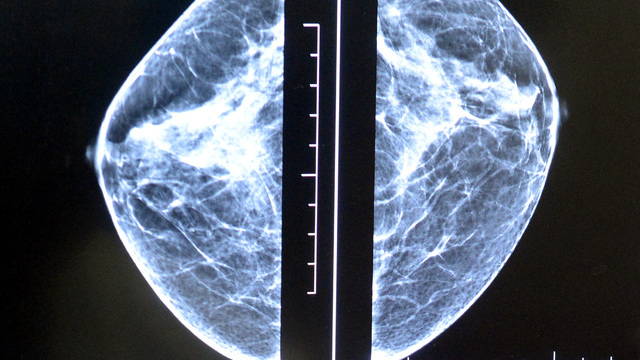

Ranné správy Presná diagnostika zvyšuje šance. Slovenskí vedci pracujú na novom teste, dokážeme zistiť včasnejšie rakovinu prsníka? 24.9.2024 08:58

Zdravie Vedci ohlasujú prelom: Nový test môže zlepšiť monitorovanie a liečbu rakoviny prsníka 5.6.2024 14:56